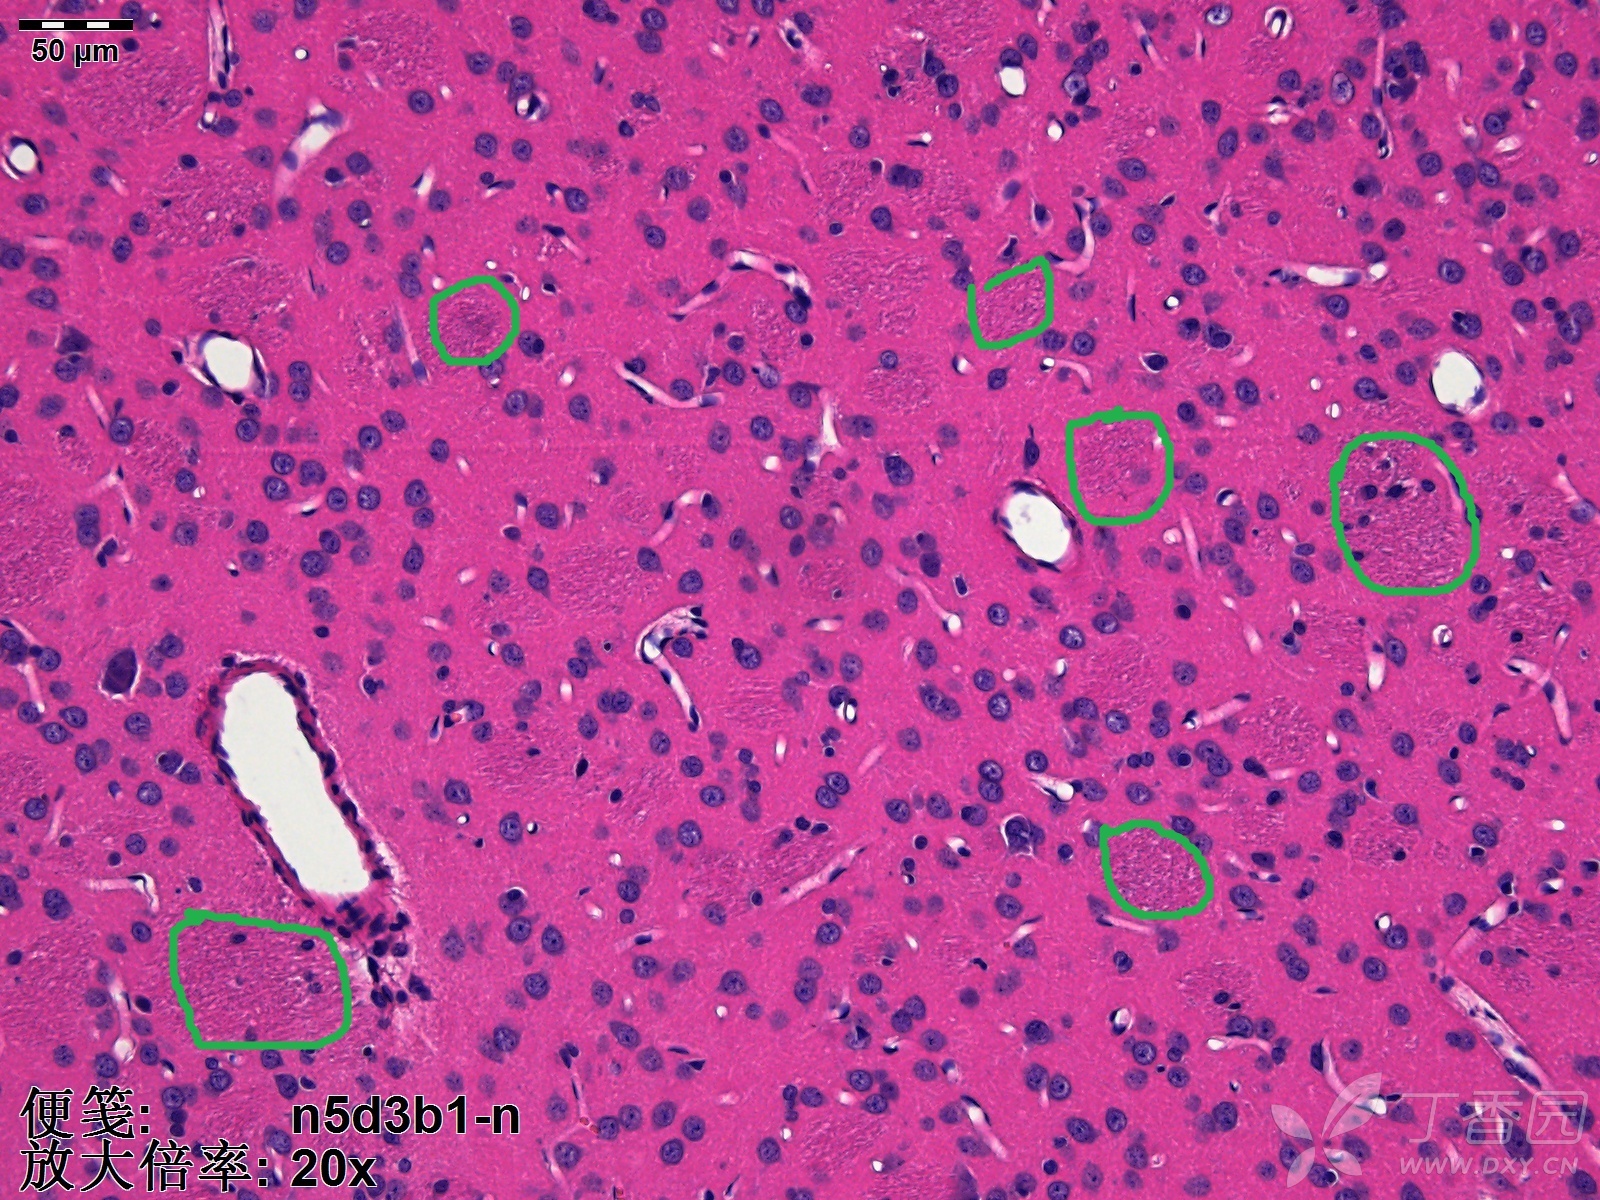

he染色,纹状体(尾壳核,cpu)区域可见一块一块的淡染色区域,请问是什么

图1,哇巴因注射入大鼠纹状体后脑组织细胞结构的变化.